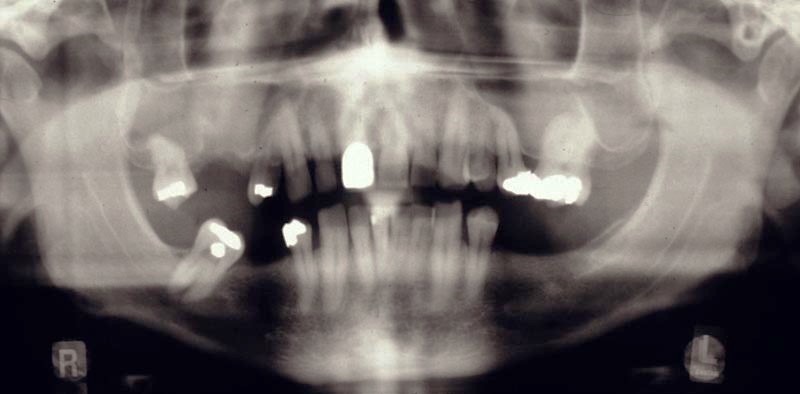

pre op assessment for risk OAC

close radiographic relation between roots and antrum

Loan standing upper molar has increased chance of communication and/or # tuberosity

Splayed roots increased chance

Arrow area – 26 can see maxillary sinus has been wrapped around the roots (less so on 16), very little bone – high chance communication and # tuberosity